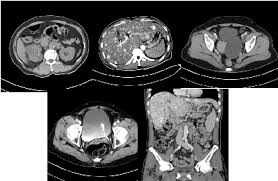

췌장암의 원발 병변 크기와 주위 침윤 정도를 파악할 수 있고 복강 내 림프절 전이, 간 전이, 복막 전이 등 췌장암의 초기 확산 평가에 유용하다.

다만 방사선 노출이 불가피하다는 단점이 있다. Ct 검사 이외에 췌장암을 조기에 진단할 수 있는 mri는 ct와 달리 방사선 노출도 없고 조영제 부작용도 거의 없고 매우 정확하지만, 검사 비용 부담이 ct에 비해 높고, 영상획득 시간이 ct보다 길기 때문에 숨을 오래 참기 힘든 사람은 정확한 촬영이 어렵다. 환자와 의료진이 췌장암 증상에 민감하게 반응해서 조기에 정밀 검사를 한 것이 한 요인인 것으로 병원 측은 분석한다. 췌장암은 초기에 발견하는 것이 어려운 질환인 만큼. 췌장암 진단에서 가장 중요한 검사는 '복부 ct(전산화단층촬영)' 검사다. 췌장암 환자의 80%는 3~4기 상태로 암을 발견한다. 췌장은 위 뒤에 붙어있는 장기다. 따라서 췌장암 위험인자가 있는 사람, 즉 췌장암 가족력이 있거나 고령, 흡연자, 당뇨, 만성 췌장염을 앓고 있는 경우 정기적으로 초음파, 복부 ct 같은 검진을 받는 게 좋다. 복부 ct는 대동맥 질환이나 간, 췌장, 신장, 대장 등의 각종 암 병변의 정확한 위치와. 초음파 검사는 통증이나 몸의 불편함에 대한 증상이 있을 때 그 원인을 찾기 위해 기본적으로 시행하는 검사입니다. 췌장암 증상 검사방법 췌장암 검사 방법 어떻게 될까요? Ct(전산화단층촬영)검사는 초음파 검사보다 췌장암을 발견하는 데 우수하다. 췌장의 종괴 및 전이 여부 등 많은 정보들을 ct로 확인할 수 있다.

전문의들은 췌장암 고위험군에 속한다면 6 개월 ~1 년마다 한 번씩 복부 ct 나 복부 초음파를 정기적으로 받는 것을 권한다. 복부 ct 검사는 췌장암의 병기 결정 (얼마나 퍼졌는가를 확인하는 과정)에 필수적인 검사이며, 현재 췌장암 진단에 가장 유용하고 정확도도 높은 검사입니다. 췌장암을 진단하는 방법으로는 복부 ct 검사와 mri 검사 방법이 있습니다. 환자의 전신 상태가 수술을 시행하지 못할 정도로 좋지 않은 경우, 복부 전산화단층촬영 (ct) 또는 자기공명영상술 (mri) 결과 중요 정맥 또는 동맥에 침범이 있어 절제가 불가능한 경우, 간 또는 복강, 기타 장기에 전이가 있어 절제가 불가능한. 췌장암은 초기에 발견하는 것이 어려운 질환인 만큼. 초음파 검사보다 췌장암을 진단하는데 더 효과적이다. Ct(전산화단층촬영)검사는 초음파 검사보다 췌장암을 발견하는 데 우수하다. 내부 장기를 더욱 세밀하고 정밀하게 관찰하는 것이 가능합니다. 진행성, 전이성 췌장암 환자는 치료가 어렵다. 췌장암 진단에서 가장 중요한 검사는 '복부 ct(전산화단층촬영)' 검사다. 경제적 여건이 허락한다면 내시경 초음파를 받는 것도 좋다. 김영선 원장 (사진=민트병원 제공) 민트병원 이미징센터 김영선 원장 (영상의학과 전문의/복부 세부전공)은 복부 초음파검사는 몸의 깊숙한 곳에 위치한 데다 위, 소장, 대장으로 가려진 췌장의 특성상 전체를 제대로 확인하기 어려울 수 있다며 ct와 mri는 고해상도 촬영이 가능해 췌장 전체를 확인할. 췌장암 진단은 혈액검사나 복부초음파검사보다는 조영 증강 복부 ct 검사, 자기공명영상(mri) 검사, 초음파내시경 검사를 통해 가능하다.